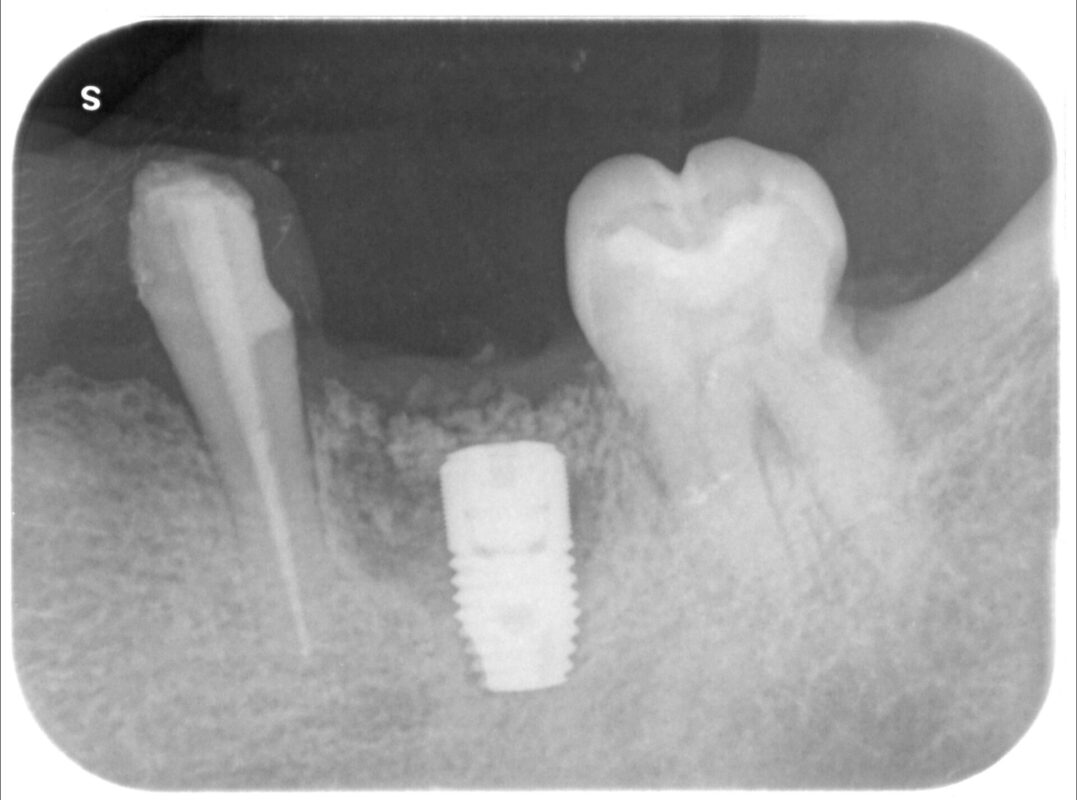

軟組織を増やす処置を行なったため、3ヶ月ほど待機してインプラント処置しました。

少し人工骨を添加しています。

処置時間は15分程度です。

4ヶ月程度待ってから仮の歯を装着するための2次オペ予定。

奥の歯牙に対する虫歯処置も必要です。

使用インプラントはアストラEV(スウェーデン)。